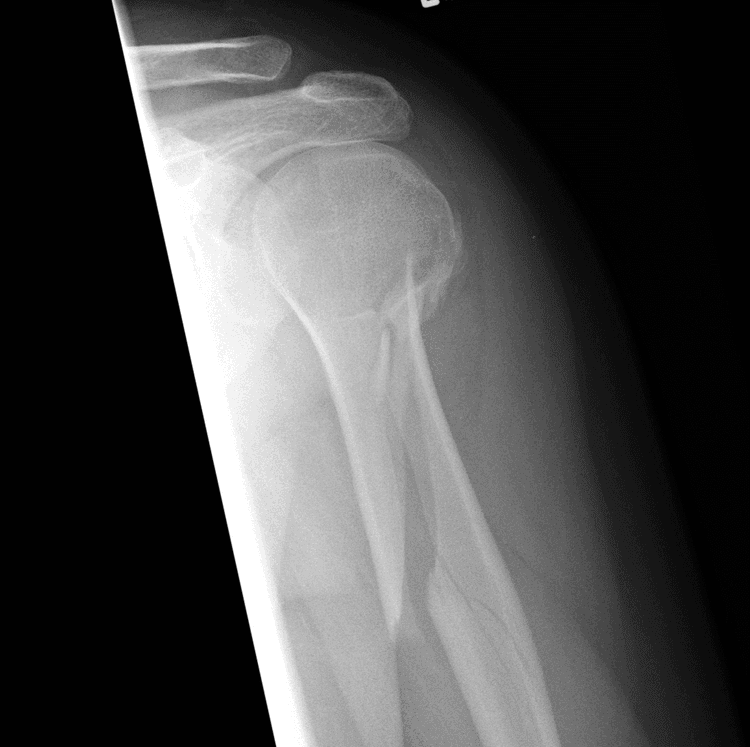

Fracture Dislocation - सांध्यातील एका हाडाला फ्रॅक्चर असल्याने सांधा निखळणे.